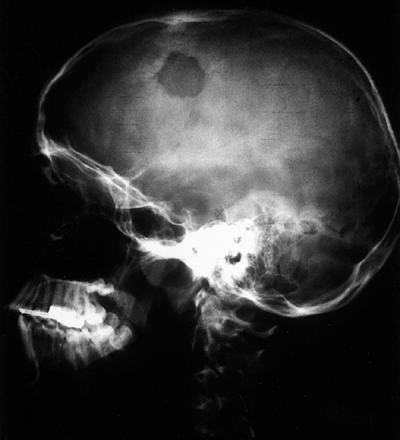

In addition, bone scanning is the most practical method of surveying

concentration of technetium-99 and produces a “hot spot” on the scan.

The technetium bone scan can be used to evaluate the activity of a

primary lesion, to search for other bone lesions, and to indicate

extension of a lesion beyond what is seen on the plain radiograph. The

activity compared with normal soft tissues. The technetium-99 bone scan

more activity than other organs. The technetium-99 scan is sensitive

but nonspecific. The principal value of a radionuclide scan is as a

means of surveying the entire skeleton for clinically unsuspected

lesions. In approximately 25% of cases of Langerhans cell histiocytosis

and plasmocytoma, the bone scan is normal, or there is decreased

activity at the site of the lesion (90, 91, 92).

Figure 14.2

An anterior view of a whole body technetium-99 bone scan. This patient has an osteoid osteoma of her talus, and there is increased activity in the talus. There is also increased activity in the distal tibia, which is thought to be a reaction to the local increased blood flow. Technetium-99 bone scanning is an efficient means of evaluating the entire skeleton of a patient with a bone lesion. It is important to have the entire skeleton scanned, rather than limit the scan to a small part of the skeleton. |